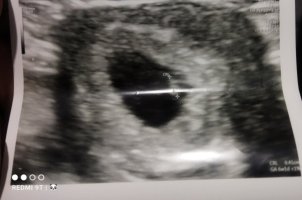

Admin inanın ne yaptım anlamadım ilk paylaştığım görüntü arkadaşımın yanlış oldu silmeyi de inanın bilmiyorum benim görüntü bu karından incelermisiniz lütfen

Hayatım tam resimde bakacağım yer parlamış bir şey göremiyorum başka resim yüklemen mümkün olur ise değerlendirmek isterim.

Suda var benim elim titriyor galiba netlestiremiyorum. Aslında şuan çok net fakat yükleme esnasında mi bulaniklasiyor anlamadım.